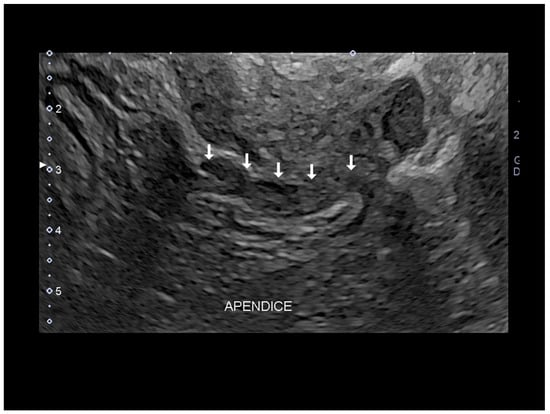

Figure 13. Endometriosis of appendix (see thin and thick white arrow) confirmed at surgery (AD).

Figure 15. Endometriosis of appendix (see white arrow) by transvaginal endometriosis confirmed at surgery.

3.1. Endometriosis of the Appendix

The appendix is also an unusual site of extra-pelvic endometriosis. Endometriotic lesions affecting this area may be asymptomatic or may provoke acute appendicitis, melena, ruptured bowel or obstructed bowel from intussusception. Appendiceal endometriosis has a typical histopathological appearance: the mucosa is always left unscathed while the endometrial glands, stroma and hemorrhagic foci are gathered in the muscular and seromuscular layers [24]. Appendiceal endometriosis may have similarities with the clinical presentation of diverticular disease, colorectal cancer, inflammatory bowel disease, carcinoid tumors, benign intramural neoplasms, occult intra-abdominal metastases, mesenteric neoplasms and pelvic abscesses [25]. In ultrasonography appendiceal endometriosis is characterized by a solid lesion in the wall of small bowel, usually well defined (Figure 12, Figure 13, Figure 14 and Figure 15).